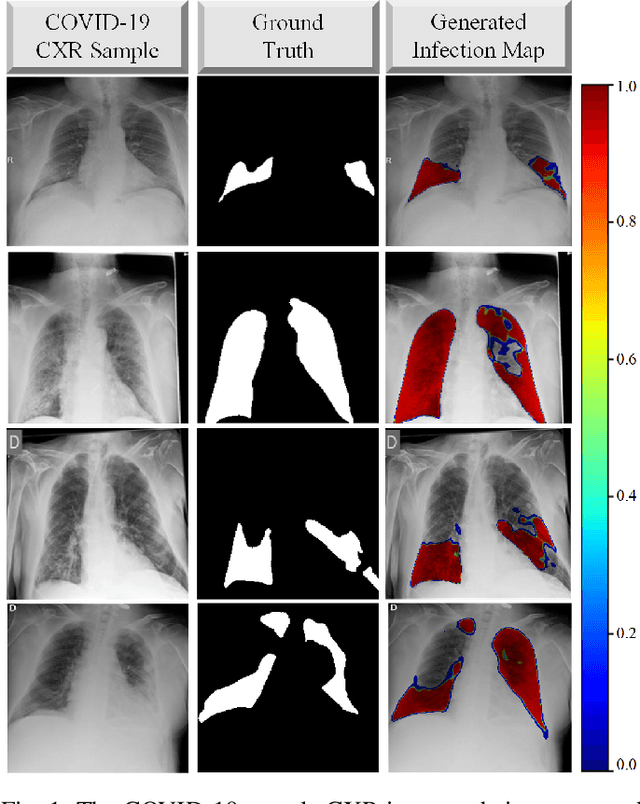

Abstract:Computer-aided diagnosis has become a necessity for accurate and immediate coronavirus disease 2019 (COVID-19) detection to aid treatment and prevent the spread of the virus. Compared to other diagnosis methodologies, chest X-ray (CXR) imaging is an advantageous tool since it is fast, low-cost, and easily accessible. Thus, CXR has a great potential not only to help diagnose COVID-19 but also to track the progression of the disease. Numerous studies have proposed to use Deep Learning techniques for COVID-19 diagnosis. However, they have used very limited CXR image repositories for evaluation with a small number, a few hundreds, of COVID-19 samples. Moreover, these methods can neither localize nor grade the severity of COVID-19 infection. For this purpose, recent studies proposed to explore the activation maps of deep networks. However, they remain inaccurate for localizing the actual infestation making them unreliable for clinical use. This study proposes a novel method for the joint localization, severity grading, and detection of COVID-19 from CXR images by generating the so-called infection maps that can accurately localize and grade the severity of COVID-19 infection. To accomplish this, we have compiled the largest COVID-19 dataset up to date with 2951 COVID-19 CXR images, where the annotation of the ground-truth segmentation masks is performed on CXRs by a novel collaborative expert human-machine approach. Furthermore, we publicly release the first CXR dataset with the ground-truth segmentation masks of the COVID-19 infected regions. A detailed set of experiments show that state-of-the-art segmentation networks can learn to localize COVID-19 infection with an F1-score of 85.81%, that is significantly superior to the activation maps created by the previous methods. Finally, the proposed approach achieved a COVID-19 detection performance with 98.37% sensitivity and 99.16% specificity.